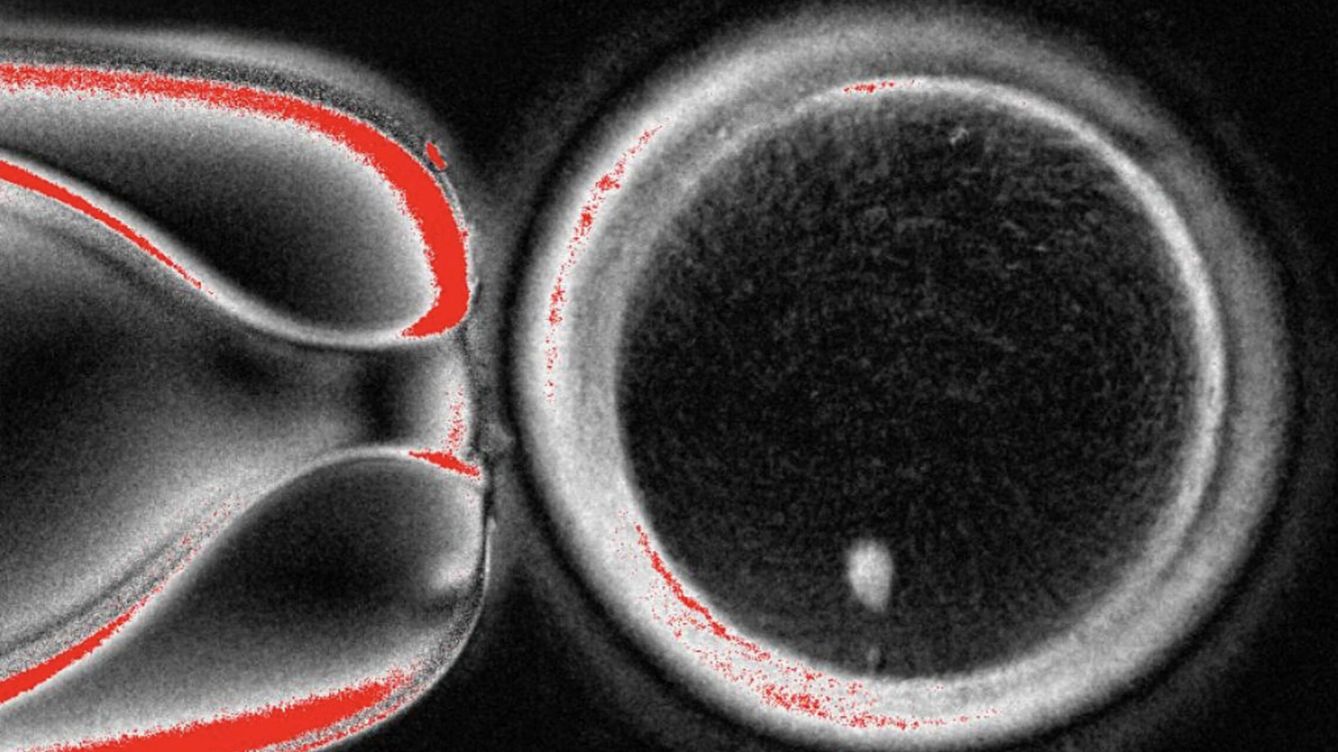

El procedimiento consistió en transferir el núcleo de una célula de piel humana a un óvulo previamente enucleado, es decir, al que se le había retirado su propio núcleo. De este modo, los investigadores reconstruyeron 82 óvulos artificiales, que luego fueron fecundados con esperma donado.

Alrededor del 9% de los embriones resultantes lograron desarrollarse hasta la etapa de blastocisto, correspondiente a los primeros seis días del desarrollo embrionario, lo que representa un avance notable en la investigación básica sobre la fertilidad.